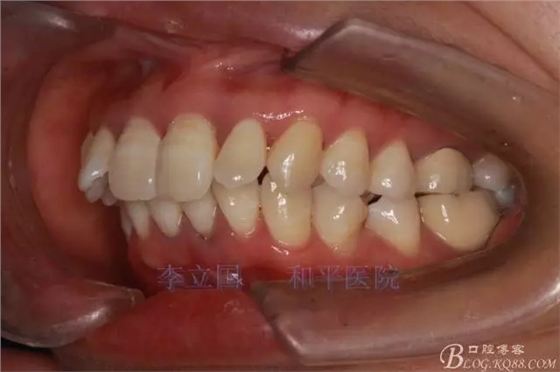

患者主訴前突。

1.患者上前牙直立,面型前突,典型的嘴凸牙不吐,關(guān)鍵是前牙轉(zhuǎn)矩控制,建議使用高轉(zhuǎn)矩托槽。

2.磨牙關(guān)系一側(cè)完全遠(yuǎn)中,一側(cè)遠(yuǎn)中尖対尖,采用兩個(gè)上4,一個(gè)下1的拔牙模式。